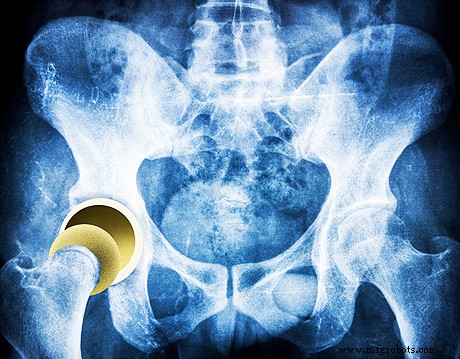

Orthopedics: Next‑Generation Joint Coatings

Artificial joints often rely on cobalt, chromium, or nickel alloys, which may trigger hypersensitivity in susceptible patients. Diamond coatings eliminate this risk while adding antibacterial properties that reduce post‑operative infection rates. Clinical studies published in 2022 demonstrate that diamond‑coated prostheses exhibit lower wear particle release and improved patient outcomes compared to conventional alloys.